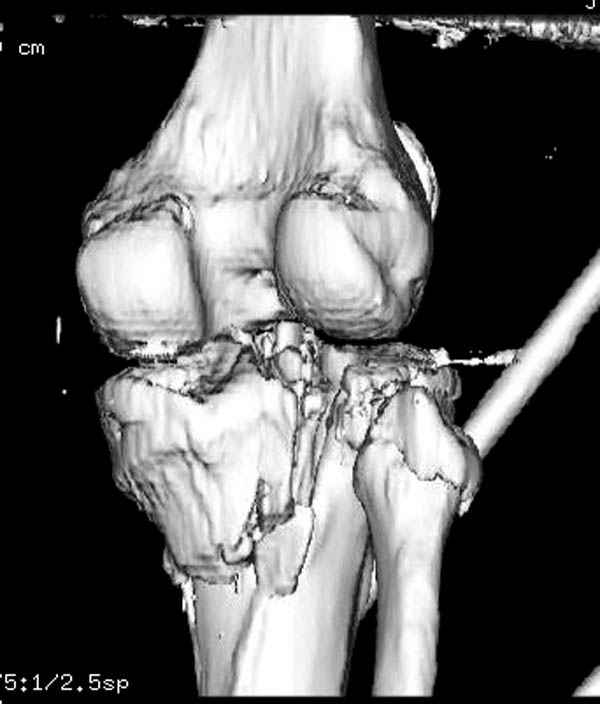

Здесь как раз тот случай, когда результат зависит не только от мастерства хирурга, но и от наличия современных методов исследования. Например, КТ которая поможет рассчитать направления шурупов и установку импланта. Кроме этого, поможет определиться с доступом.

На представленных предоперационных срезах КТ огромный задне-медиальный фрагмент расположен больше кзади, чем медиально. Для планирования, кроме поперечных срезов, надо ориентироваться на корональные срезы, которые укажут топографию верхушки медиального фрагмента.

При сложных переломах тибиал плато для своего рода Damage Control мы иногда применяем поэтапную тактику. Сперва оперируется одна сторона, а потом после рекондиции мягких тканей окончательный этап.

Доступ к медиальной стороне задний или медиальный, через pes или в пространстве между medial gastroc мышцы.